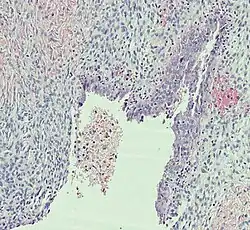

Histopathology

In case an ovarian cyst is surgically removed, a more definite diagnosis can be made by histopathology:

Functional cyst | Follicular cyst |

|